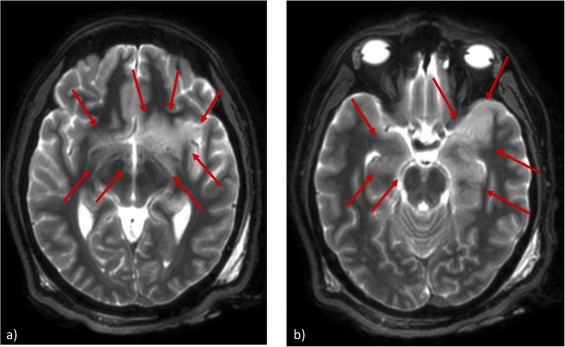

就外觀而言,男子的屍體沒有任何病灶。驗屍團隊本來想照慣例,先做電腦斷層掃描(computed tomography),觀察內部概況後再解剖。無奈這天儀器故障,所以改照核磁共振造影(magnetic resonance imaging)。不過,塞翁失馬,焉知非福。雖然核磁共振的成本較高,費時冗長,但是影像更為細緻:神經放射科醫師指出腦部額葉與顳葉的扣帶皮質、邊緣葉,以及島葉皮質的左側,都有損傷。換句話說,可能是單純疱疹病毒腦炎(herpes simplex virus encephalitis)。[1]

男子的 T2 核磁共振影像。圖/參考資料 1,Figure 4(CC BY 4.0)

照完醫療影像,把屍體剖開來,有肉眼和顯微鏡都可見的肺炎(pneumonia)病變。腦部切片的組織學分析,以蘇木紫(hematoxylin)和伊紅(eosin)染劑上色,顯現出少量發炎的腦幹細胞與病變的海馬體神經元;透過免疫組織化學染色,則發現腦幹內有某些類型的 T 細胞和巨噬細胞,以及活化的小神經膠質細胞等多種免疫細胞。更重要的是,在海馬體中找到單純疱疹病毒(herpes simplex virus)HSV-1 與 HSV-2,證明了根據核磁共振影像所做的推測。[1]

單純疱疹病毒腦炎的成人發病率高,每年約有 1/250,000–1/500,000;而且就算即時診斷,並經靜脈施予抗病毒藥物 acyclovir,仍有 20% 到 30% 的死亡率。[4]其診斷方式為執行腰椎穿刺(lumbar puncture),抽取腦脊髓液來檢驗有無病毒;以及做腦部核磁共振,主要看額葉與顳葉是否病變,僅有少數病例會擴及腦幹。病毒影響腦部,展現出來就成了頭疼、癲癇、發燒、失語、個性改變或精神錯亂。[1]

問題是這名男子生前大概缺乏明顯症狀,所以未曾就診。難怪 2023 年在《國際鑑識科學:報告》(Forensic Science International: Reports)期刊介紹此案的論文作者,只差沒抱怨如此隱蔽的疾患,要叫人怎麼猜。他們最後表示男子死於肺炎,卻通篇討論他罹患的單純疱疹病毒腦炎,並且強調多數鑑識單位頂多幫屍體照電腦斷層掃描,不太容易發現這種腦部感染,所幸他們的電腦斷層掃描儀壞掉,仰賴核磁共振才做出正確診斷。[1]